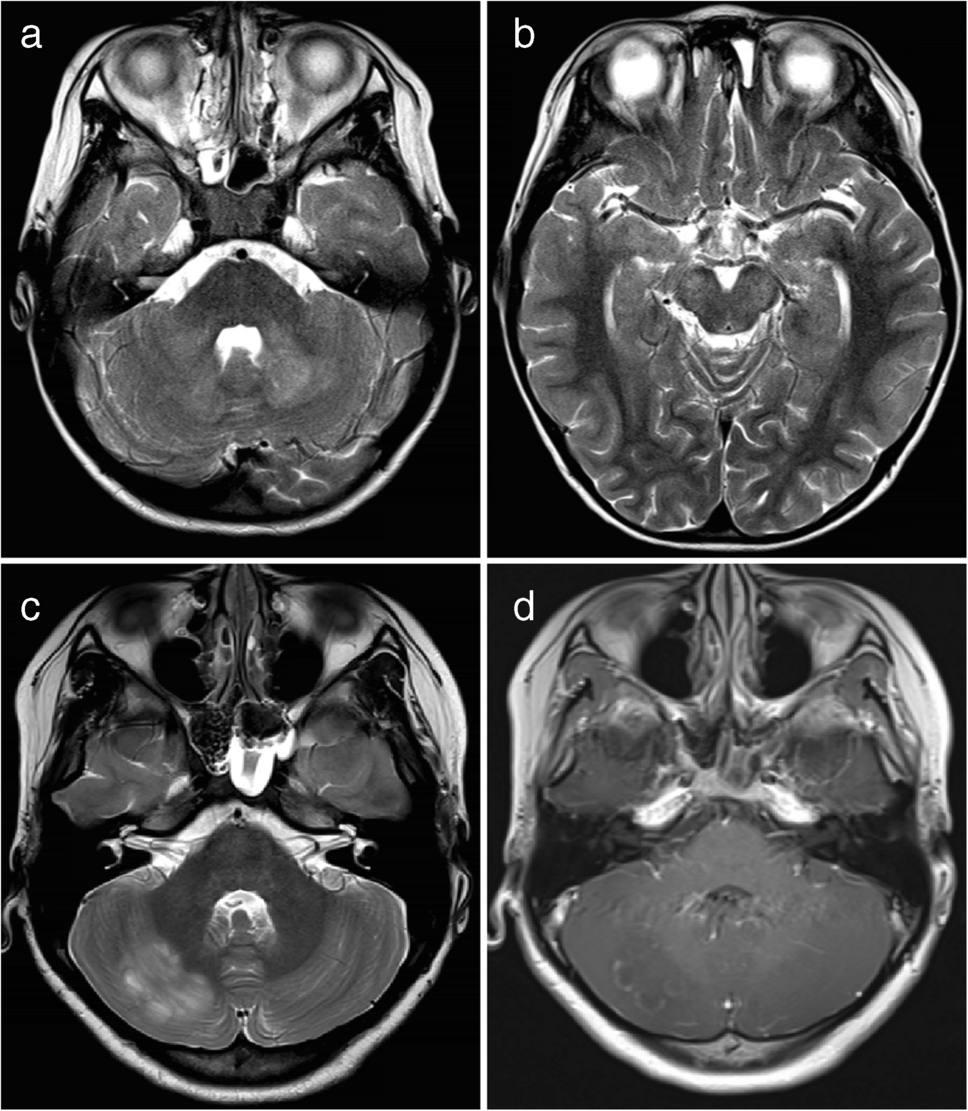

A cortical encephalitis pattern was identified in three patients, and an aseptic meningitis pattern was seen in six patients (Figs. 4 and 5, respectively). Tumefactive demyelinating lesions were observed in three cases. These lesions were large (> 2 cm) and unifocal, resembling either neoplastic processes or localized abscesses (Fig. 6). The lesions were located in the periventricular white matter, thalamus, and subcortical white matter/cortex, respectively. Unlike typical tumors, these lesions did not demonstrate mass effect. A cerebellitis/brainstem encephalitis pattern was found in two patients (Fig. 7). One patient exhibited non-enhancing lesions in the cerebellar white matter and midbrain, while the other had poorly defined cerebellar cortical lesions with curvilinear enhancement. Among the miscellaneous patterns, one patient showed a leukodystrophy-like presentation (Fig. 8a), and another exhibited an MS-like pattern (Fig. 8b–d).

Fig. 7

Magnetic resonance images illustrate myelin oligodendrocyte glycoprotein antibody-associated diseases with a cerebellitis/brainstem encephalitis pattern. a, b Axial T2-weighted images obtained at the fourth ventricle level (a) and the midbrain level (b) in a 5-year-old boy with dizziness show bilateral lesions in the cerebellar white matter (arrows in a) and midbrain (arrows in b). c, d Axial T2-weighted (c) and post-contrast T1-weighted (d) images in a 12-year-old girl with isolated cerebellitis show an ill-defined hyperintense lesion (arrow in c) in the right cerebellar cortex with curvilinear enhancement (arrow in d)

Fig. 8

Magnetic resonance images illustrate myelin oligodendrocyte glycoprotein antibody-associated diseases of minor imaging patterns: a leukodystrophy-like pattern and a multiple sclerosis-like pattern. a Leukodystrophy-like pattern. Axial fluid-attenuated inversion recovery image from a 3-year-old girl with slurred speech, drooling, and right-sided weakness shows extensive, confluent, nearly symmetric white matter lesions resembling leukodystrophy. b, c, d Multiple sclerosis-like pattern. Three consecutive sagittal fluid-attenuated inversion recovery images from a 14-year-old boy demonstrate well-defined white matter lesions oriented perpendicular to the ventricles